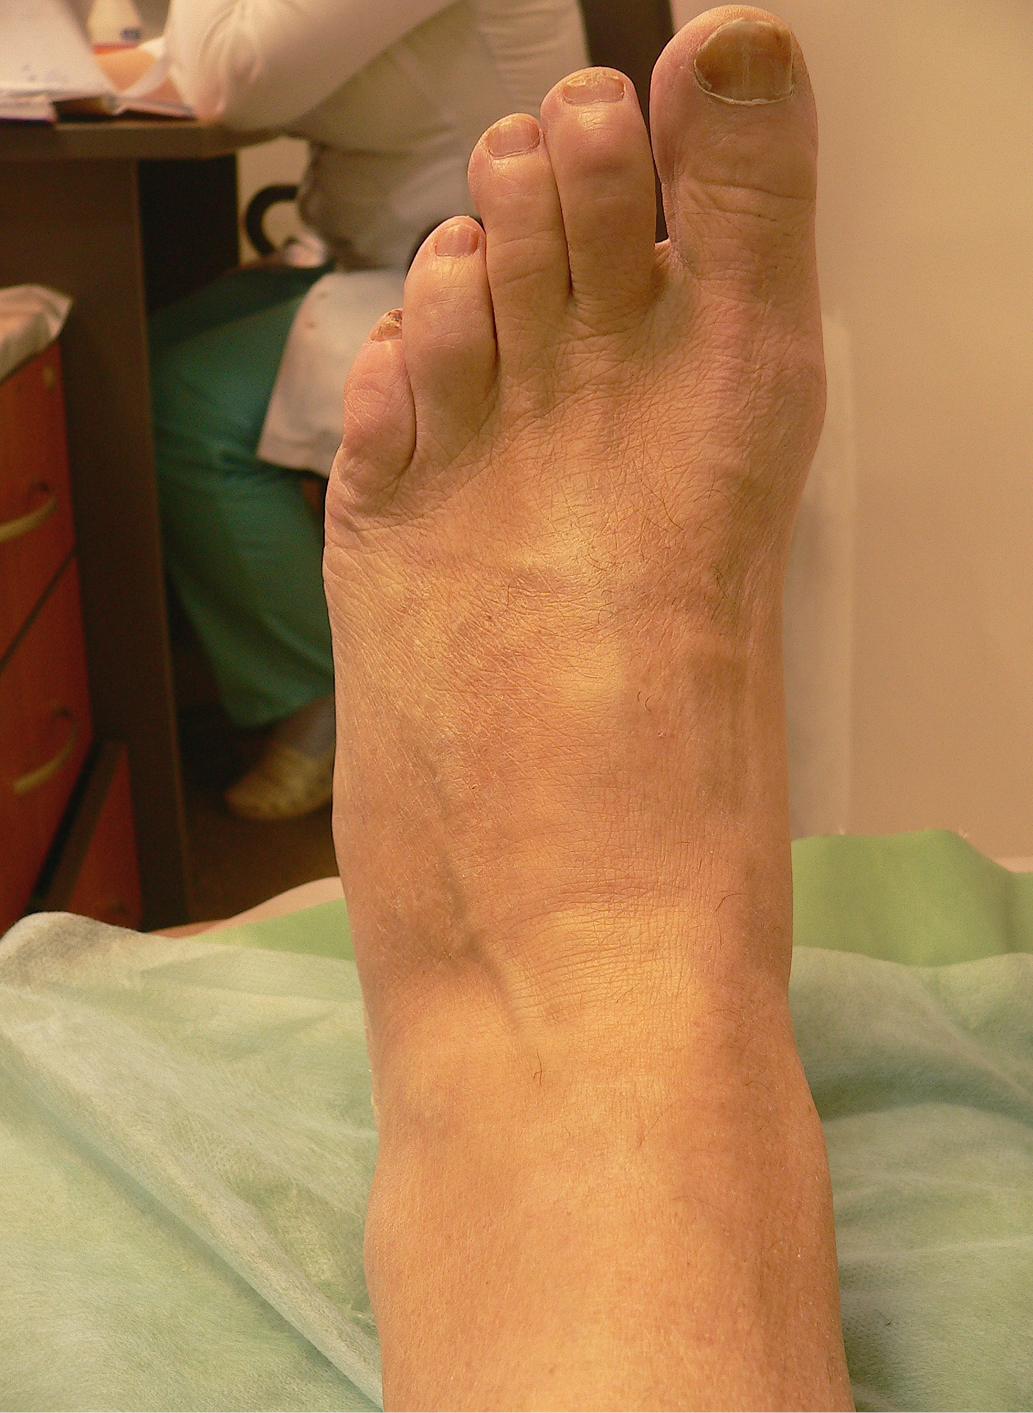

Рост 171 см, масса тела 92 кг. Определяется отек левой стопы и голеностопного сустава, пульсация артерий стоп справа ослаблена, слева отсутствует (рис. 1). Чувствительность к 10-граммовому монофиламенту, вибрационная, болевая и температурная чувствительность отсутствуют. Ахилловы рефлексы не вызываются. Балл по шкале модифицированного Нейропатического Дисфункционального Счета (НДСм)=10. Температурный градиент в пользу левой стопы=4,1°С. Отчетливой деформации продольных сводов стоп нет при уплощении поперечных сводов.

Рис. 1. Стопа пациента 1 при первом осмотре.

Жалобы на умеренную боль при опоре на стопу и отечность левой нижней конечности. Рост 196 см, масса тела 125 кг. Определяются выраженный отек стопы и голени, легкая деформация медиального свода, отклонение оси стопы латерально по отношению к голени. Вибрационная, болевая, температурная чувствительность, ахилловы рефлексы отсутствуют, так же, как и чувствительность к 10-граммовому монофиламенту (балл по шкале НДСм=10). Пульс на артерии тыла стопы и на задней большеберцовой артерии не определяется. Температурный градиент +2,2°С в пользу левой стопы (рис. 4).

Рис. 4. Стопа пациента 2 при первом осмотре.